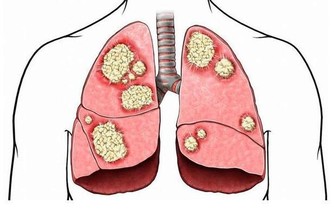

***5.增強免疫力***

維生素C還可以清除自由基,能使人體免受自由基的侵害,從多方面提高人體抗病能力,在流行性病季節適當補充維生素C能有效預防感冒,和流行病。